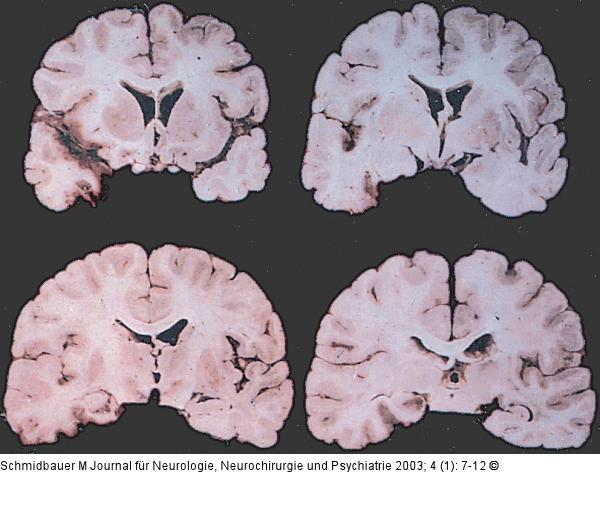

Abbildung 5: Temporallappenenzephalitis

Typischer - allerdings nur einseitiger - makroskopischer Aspekt einer Temporallappenenzephalitis durch HSV |